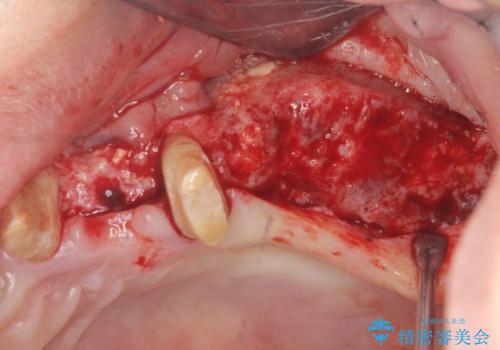

予後の悪く保存の難しい歯を抜去し、骨の造成を含んだインプラント治療を計画します。

骨の造成を行ったことで歯肉のラインは平らになり、清掃性の高い歯周環境を作り出すことができました。